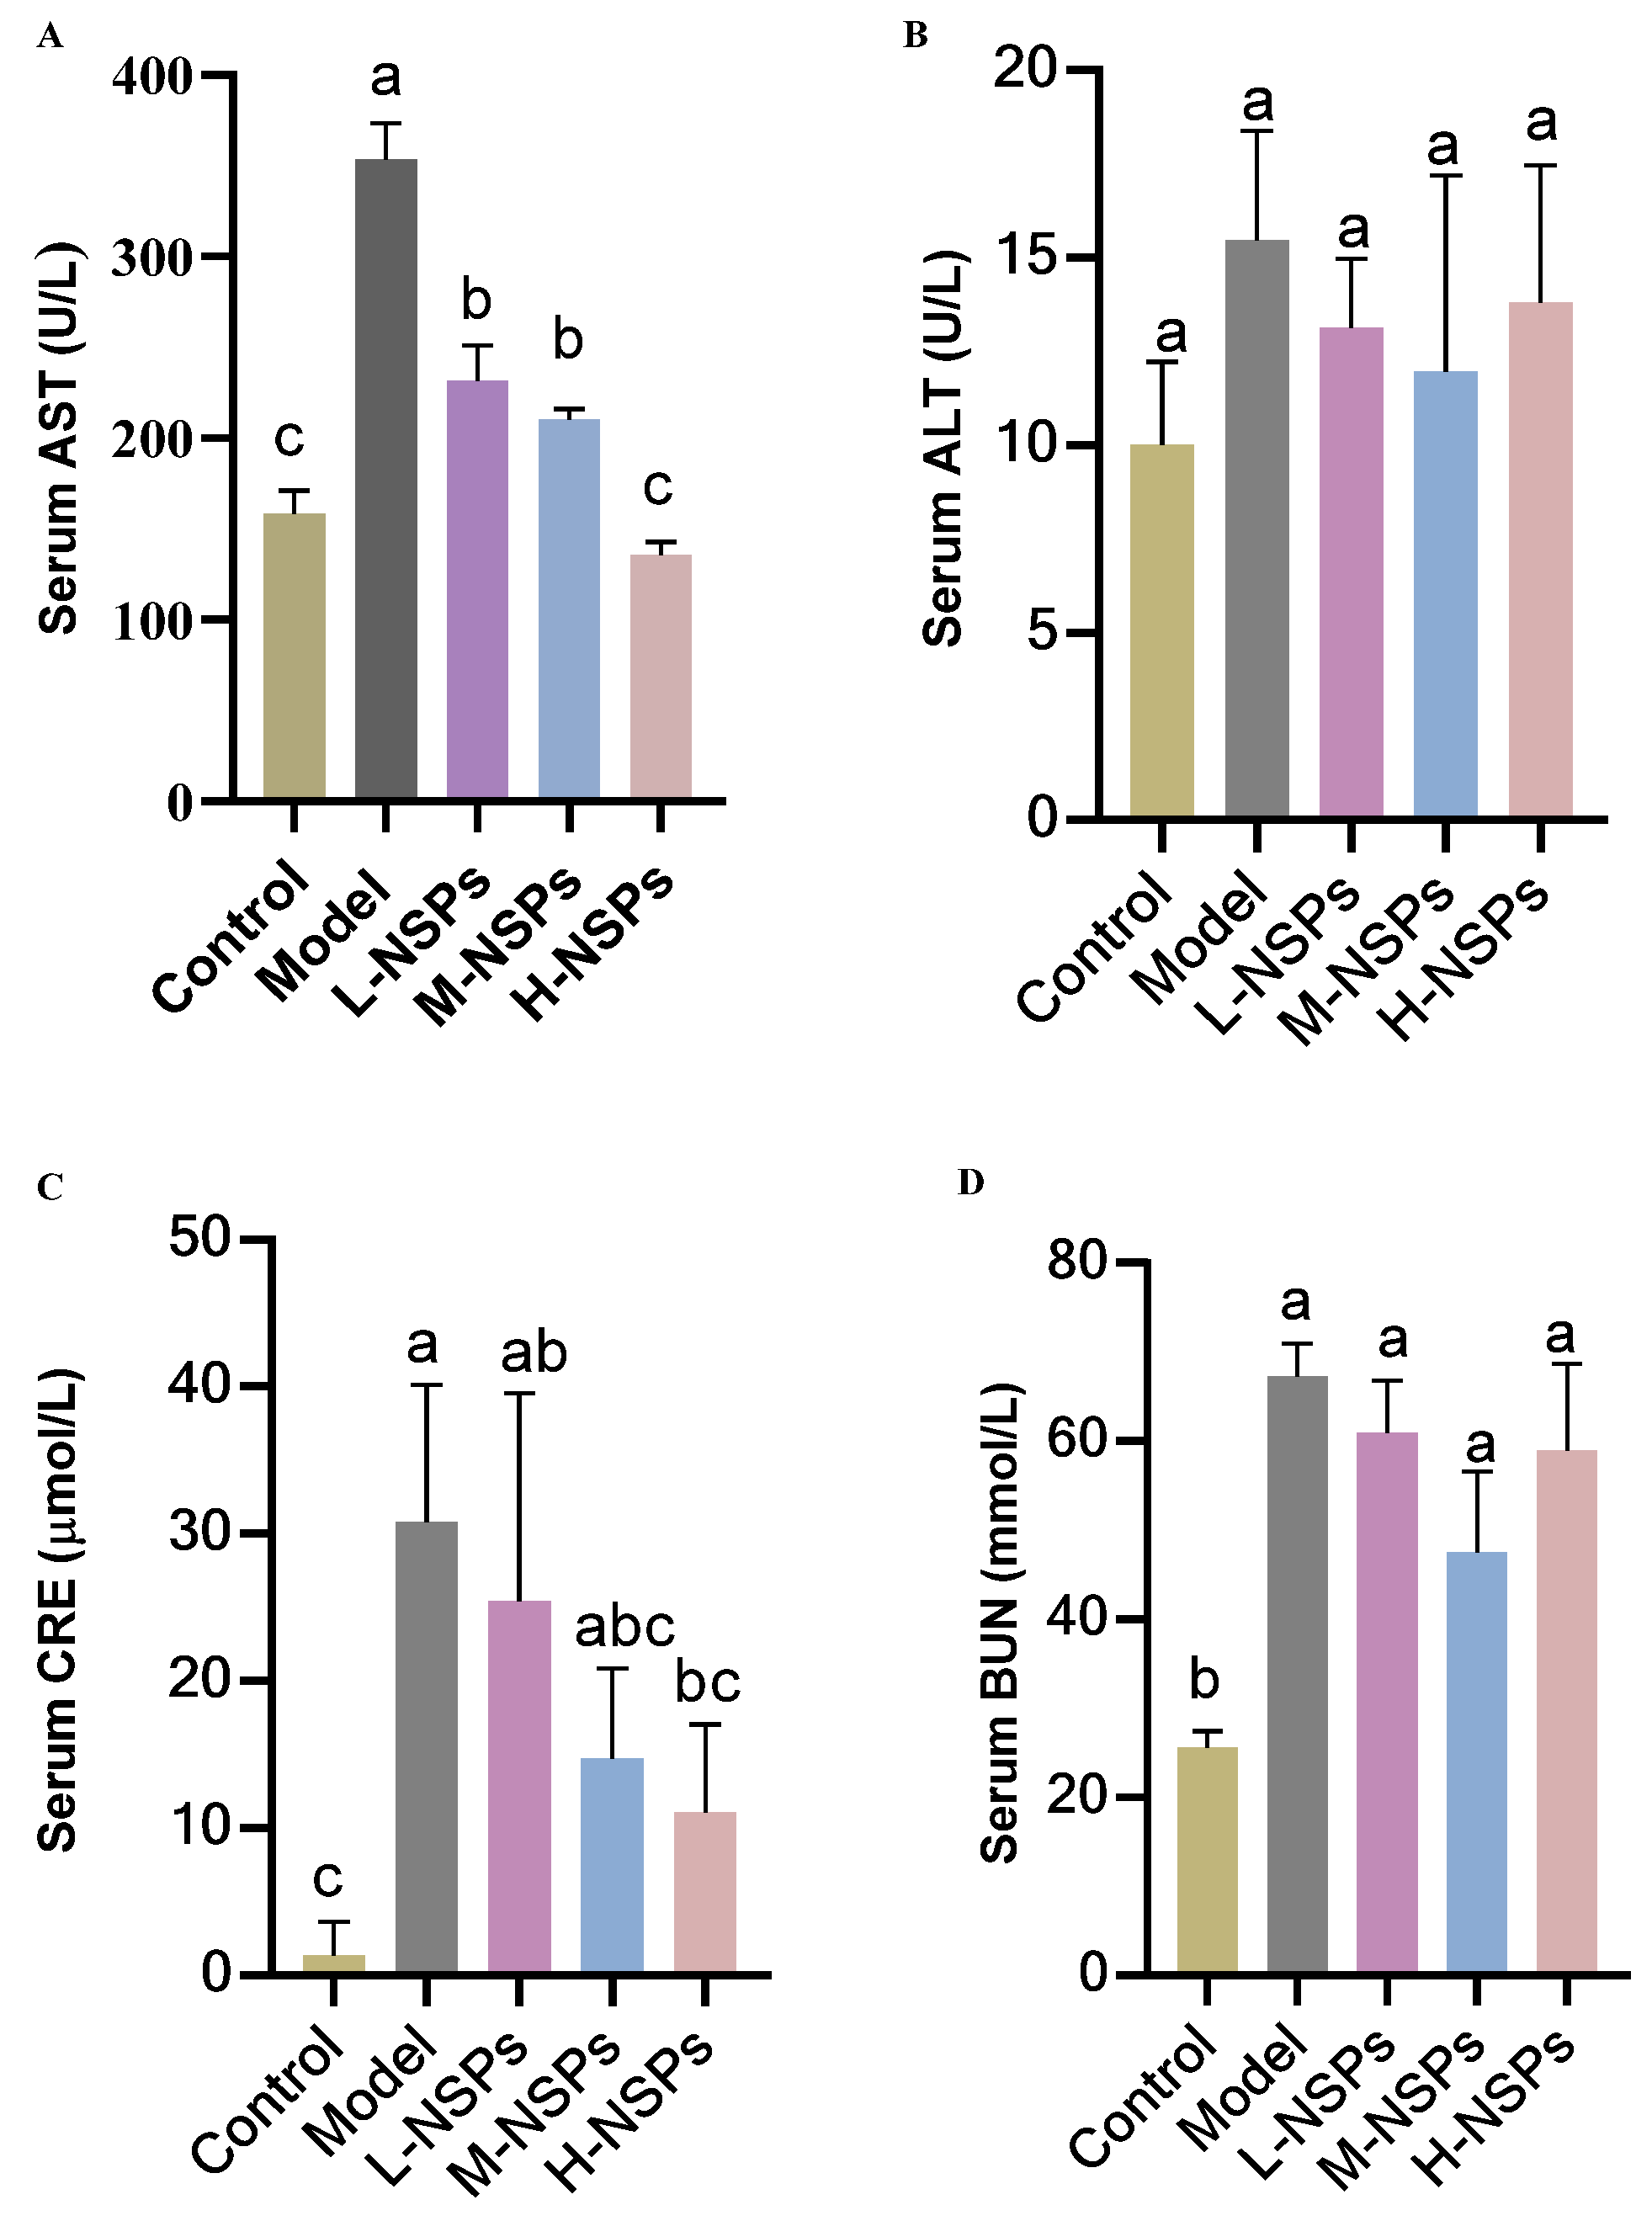

3.8. The Effect of NSPs on Hepatic Enzyme Levels

3.9. The Effect of NSPs on Renal Enzyme Levels